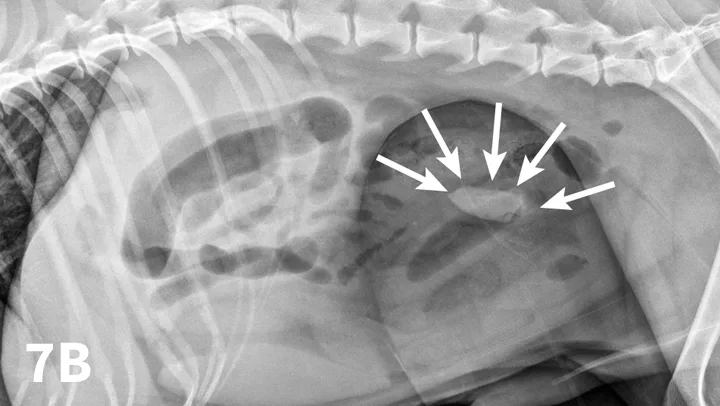

5. Conduct Compression Radiography

Left lateral radiograph of a 9-year-old Jack Russell terrier with a 4-day history of vomiting and anorexia (A). Moderate dilation with small gas bubbles (stars) of the small intestinal tract is noted (B). Left lateral compression radiograph of the same dog. A wooden spoon was used to apply compression to the caudal abdomen. Ventral to the colon, a well-defined ovoid mineral opacity (arrows) is visible within a dilated small intestinal loop. This was a piece of rubber confirmed at surgery.

With the patient in lateral recumbency and using a wooden or plastic spoon or paddle, the abdomen is mildly compressed in an area of concern identified on survey films (Figure 7A). Using the paddle and compression, adjacent bowel or masses are displaced to increase radiographic conspicuity. This results in better visualization of potential foreign material (Figure 7B), plication of small intestinal loops in cases of linear FBs, or intestinal masses otherwise obscured by superimposed bowel.